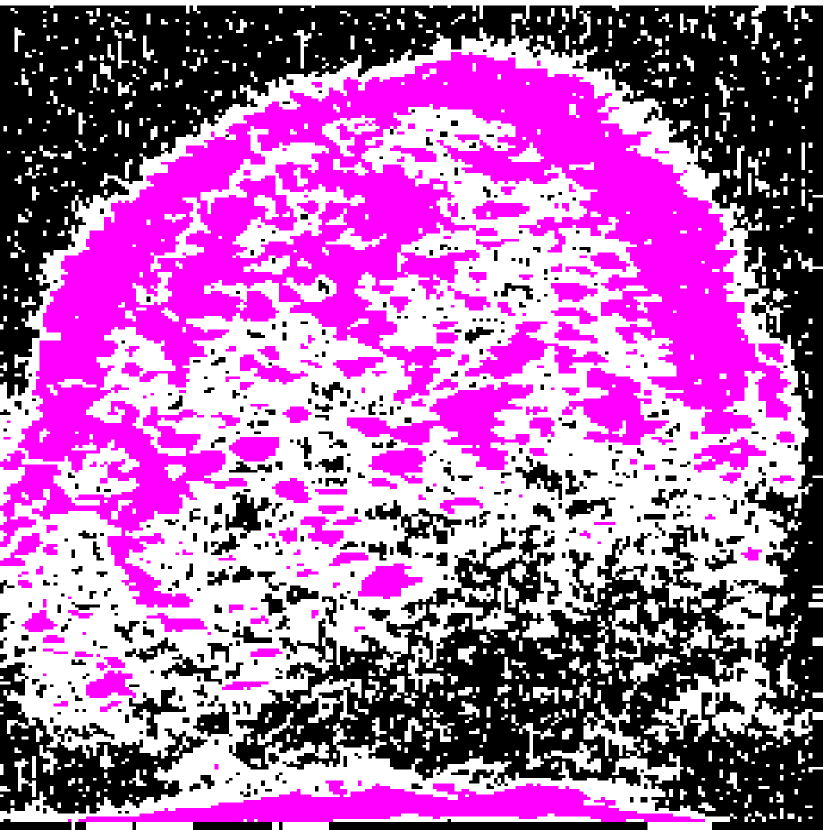

Figure 2: (a) Target HFU image. (b) Manual-segmentation result. (c) The segmentation result obtained by NGC with depth-dependent profile.

Intensity-distribution estimation is another challenge in LN segmentation. To obtain satisfactory segmentation, accurate intensity distributions for the three components of isolated LNs are required. Some clustering algorithms, such as K-means or expectation maximization (EM), may be able to categorize the intensity values of all voxels into three distributions to represent target objects. However, these approaches often yield unsatisfactory segmentation results for larger LNs (Figure 1(c)), where the intensity distribution fluctuates significantly with depth because of acoustic attenuation and focusing effects. In addition, attenuation effects may become so extreme that fat boundaries become invisible. (See the red arrow in Figure 1(a).) To mitigate the attenuation and missing-boundary problems, we used depth-dependent intensity profiles to model the depth-dependent variation of intensity mean and standard deviation in our prior work [11]. Using an expectation-maximization (EM) -based iterative framework, depth-dependent profiles were estimated by a spline-based fitting process from the previous segmentation result, and the segmentation result was obtained by NGC using the estimated depth-dependent profiles. Instead of using an EM-based framework to update profiles, level-set-based approaches can also update profiles during deformation. Bui et al. developed a method, which applied depth-dependent profiles, called statistical transverse slice level-set (STS-LS) [15]. Nevertheless, depth-dependent profiles are unable to deal with intensity inconsistency within the same depth caused by inhomogeneous acoustic attenuation as shown in Figure 2. Figure 2(c) shows the segmentation result obtained using a depth-dependent profile [11]. Compared to the manual segmentation result in Figure 2(b), some fat regions (red arrow) are mislabeled as LNP because the fat on the right (green arrow) at the same depth is much brighter than the fat on the left. In this case, depth-dependent profiles are unable to model the intensity variations accurately. Using local distribution to differentiate LNP and the fat can solve the error caused by intensity inconsistency within the same depth. Bui et al. has used a local-region-based, gamma distribution to segment LNs [13]. Level-set-based methods is good in applying local intensity distributions to differentiate regions. Since level-set-based methods deform the contour gradually, the local distributions can be updated by the boundary accordingly. However, updating distributions in local regions is computationally expensive. Furthermore, using local-region-based distributions with level-set-based methods is likely to result in convergence to a local minimum when the image is noisy. In contrast, GC-based approaches generally set the similarity cost by predefined intensity distributions. Because the boundary is unknown, the local region is hard to be determined in advance.